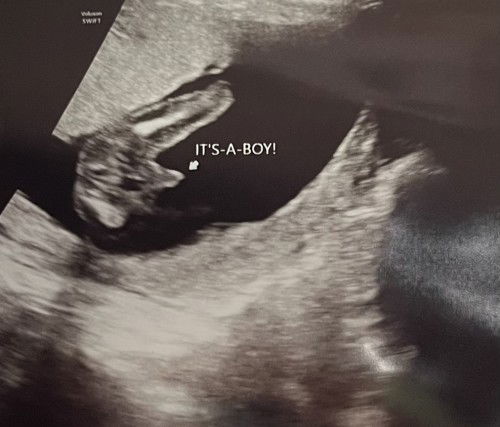

Scan gender

Nak tanya, haritu saya scan baby 17w, dr nampak baby boy, dr pon mcm yakin betul cakap baby saha baby boy, saya ada tengok kat tiktok selalunya kalau scan mcm ni mmg confirm baby boy, mummy rasa mcm mana? Sekarang dah 20w++ , saya nak start slow slow cari barang baby,

Sy msa scan 16w npk cmni boy..smlm 21w p scan mmg jelas2 npk boy..